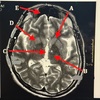

Match 1. Lentiform nucleus 2. 3rd ventricle 3. Caudate nucleus 4. Frontal sinus 5. Thalamus

A. Caudate nucleus B. Thalamus C. 3rd ventricle D. Lentiform nucleus E. Frontal sinus

A points to A. 3rd ventricle B. Basal ganglia C. Anterior horn lateral ventricle D. Posterior horn lateral ventricle

B. Basal ganglia

33

D points to A. 3rd ventricle B. Thalamus C. Lentiform nucleus D. Caudate nucleus

Lentiform nucleus